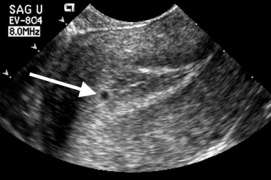

Gestational sac greater than 10mm without yolk sac

Gestational sac greater than 10mm without yolk sac Gestational sac greater than 18mm without fetal pole